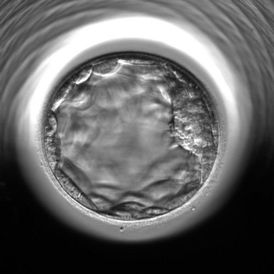

Eski tip seçimde yumurtalar bir dolabın içinde 37 derecede bekler; biz de her gün bir defa dışarı çıkartıp hangisinin daha iyi durumda olduğuna bakarak seçeriz. Şimdi yeni bir cihaz var: Embryoscope. Yapay rahim gibi düşünülebilecek bu cihaz ısı, nem, ışık vs. şartlar bakımından anne rahimini birebir taklit ediyor. Yumurta ve spermin birleştirilmesi ile elde edilen embriyolar anne adayına transfer edilinceye kadar 5 gün boyunca bu cihazın içinde korunuyor. İçerideki mikro kameralar da dakika dakika embriyoların gelişimlerini fotoğraflayarak dışarıya görüntü aktarıyor. Gelişimini takip etmemizi ve başarı şansı en yüksek olanı seçmemizi bu sağlıyor. Eski yönteme göre daha uzun süreli ve sağlıklı bir sonuca ulaşıyoruz bununla.